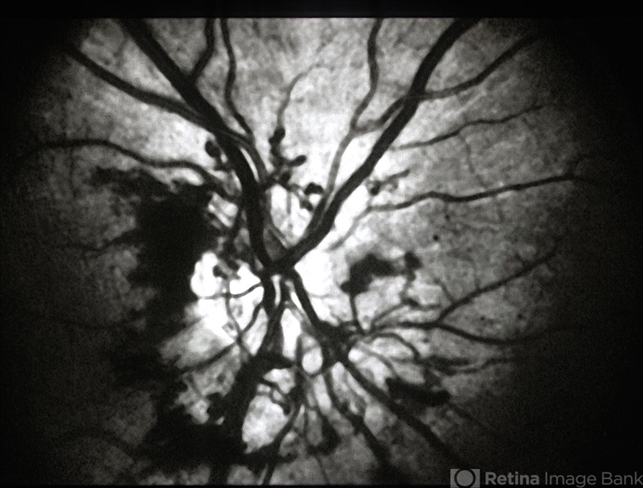

- neovascularization of the disc (NVD), cavernous hemangioma of the retina

- red-free photo of optic disc. neovascularization of the disk versus optic disc tumor (cavernous retinal hemangioma)